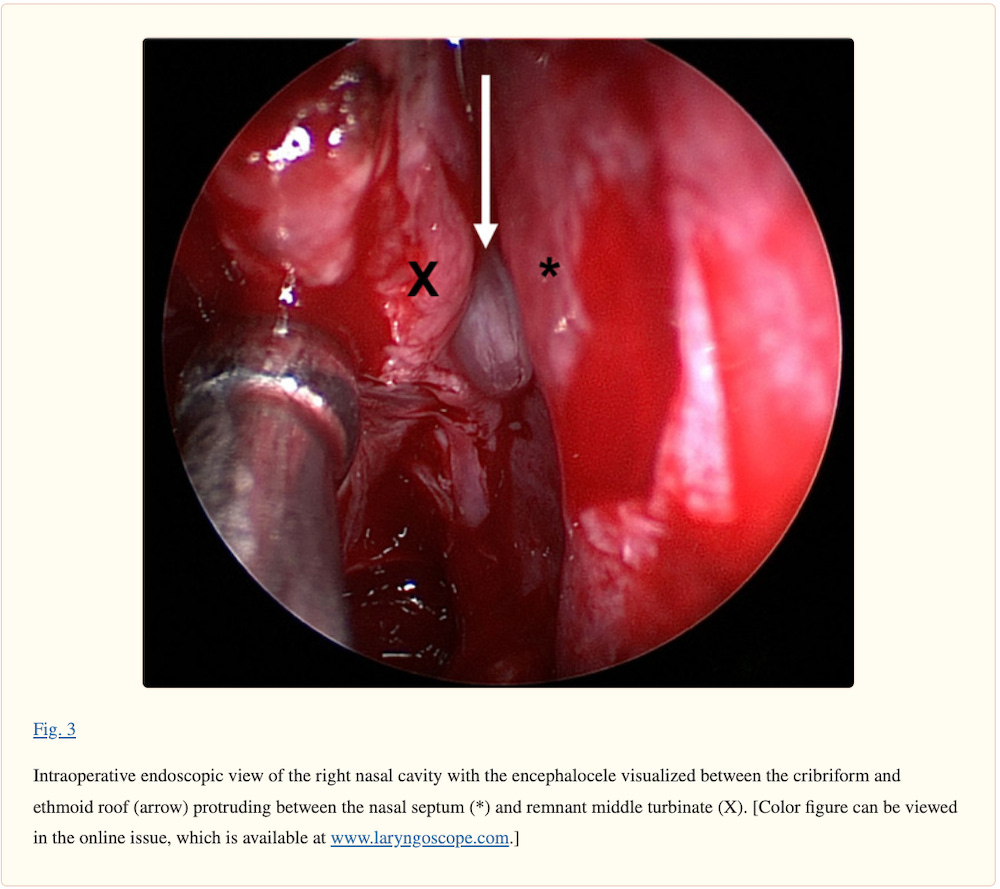

A woman in her 40s presented with unilateral rhinorrhea, metallic taste, headache, neck stiffness, and photophobia. The patient had recently completed nasal COVID-19 testing for an elective hernia repair. Shortly after, she developed unilateral rhinorrhea, headache, and vomiting. The patient’s medical history was notable for idiopathic intracranial hypertension and removal of nasal polyps over 20 years before presentation. Physical examination revealed clear rhinorrhea from the right side. Flexible nasopharyngoscopy revealed a mass in the right anterior middle meatus, but did not identify the source of the fluid. The nasal drainage tested positive for β2-transferrin.

The patient was admitted to the hospital for endoscopic surgical repair. An encephalocele was identified in the right anterior ethmoid cavity. After reduction of the encephalocele, a skull base defect in the fovea ethmoidalis was repaired with a combination of acellular human dermal matrix and a poly(D,L-lactic) acid.